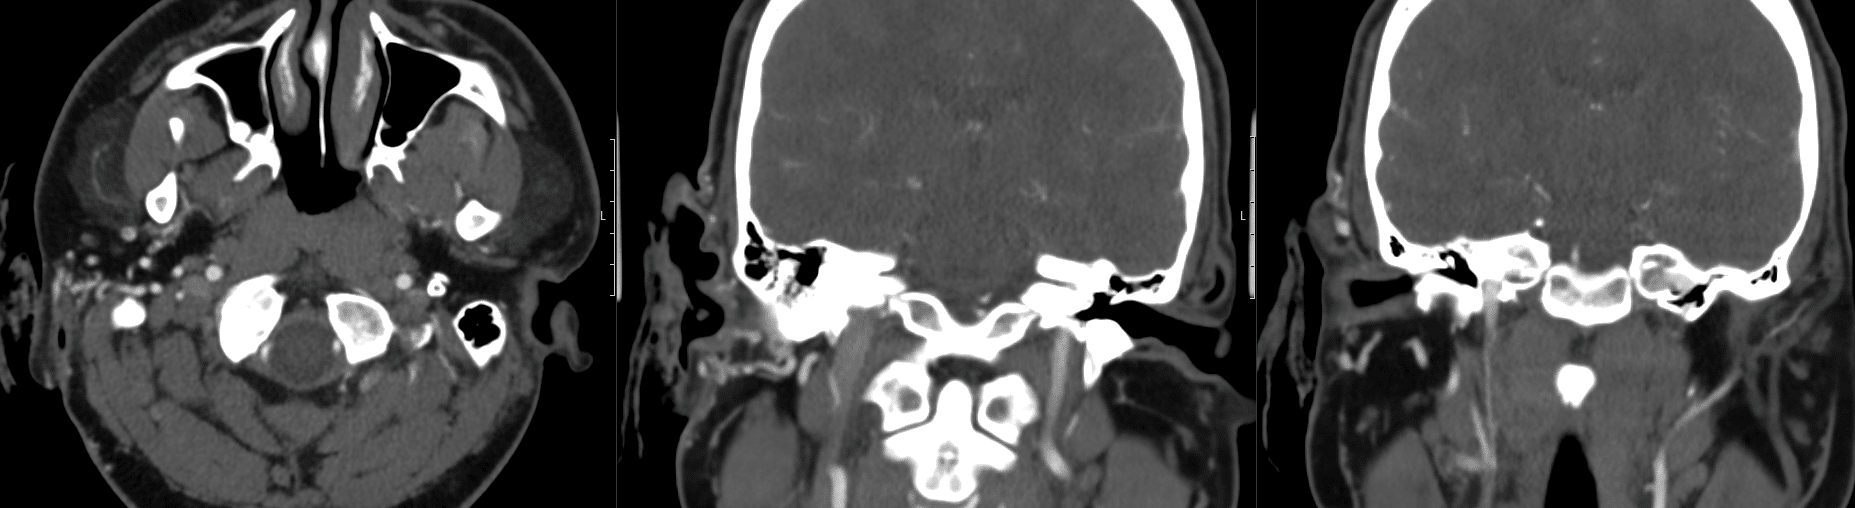

A CT angiogram of his head and neck is arranged

There appears to be a right ear arteriovenous malformation (AVM) arising from branches of the right external carotid artery. There is probably active bleeding occurring posterior to the antitragus at the time of the scan on axial image 340. Specialist ENT review without undue delay is suggested.

The internal and external carotid arteries and vertebral arteries are seen to fill. No significant stenosis is seen at the origins of the internal carotid arteries.

The M1 and M2 branches of the middle cerebral arteries, A1 and A2 branches of the anterior cerebral arteries, posterior cerebral arteries, internal carotid arteries and basilar artery are seen to fill.

There is no intraparenchymal arteriovenous malformation seen.

No intracranial arterial aneurysm is identified.